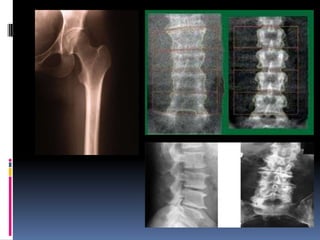

DiagnósticoHistória clínicaExame físicoAvaliação laboratorialQuadro radiográficoRX

Densitometria óssea (padrão-ouro)Índice de Singh

Quadros Radiológicos

Interpretação clínicaValores absolutosT-score – até -1,0 DP -> normal– de -1,1 a -2,5 DP -> osteopenia– abaixo de -2,5 DP -> osteoporose– abaixo de -2,5 DP na presença de fratura -> osteoporoseestabelecidaZ-score